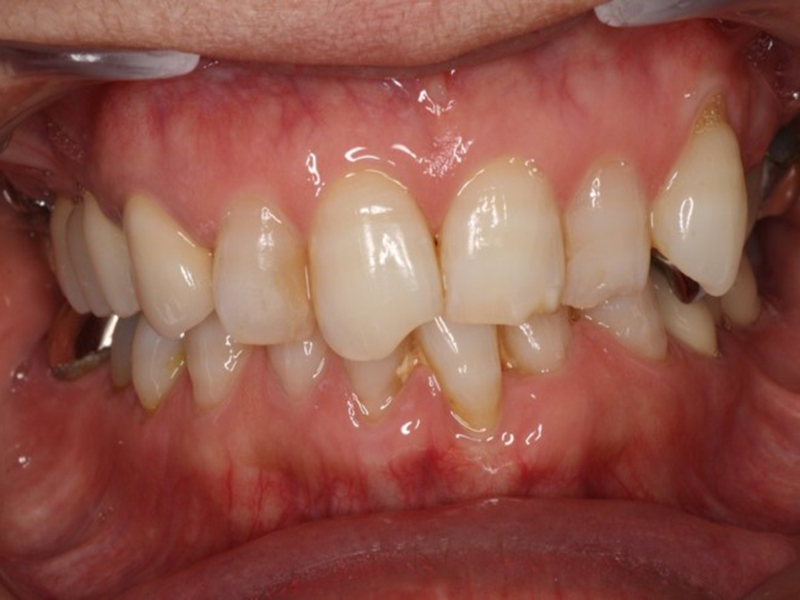

before